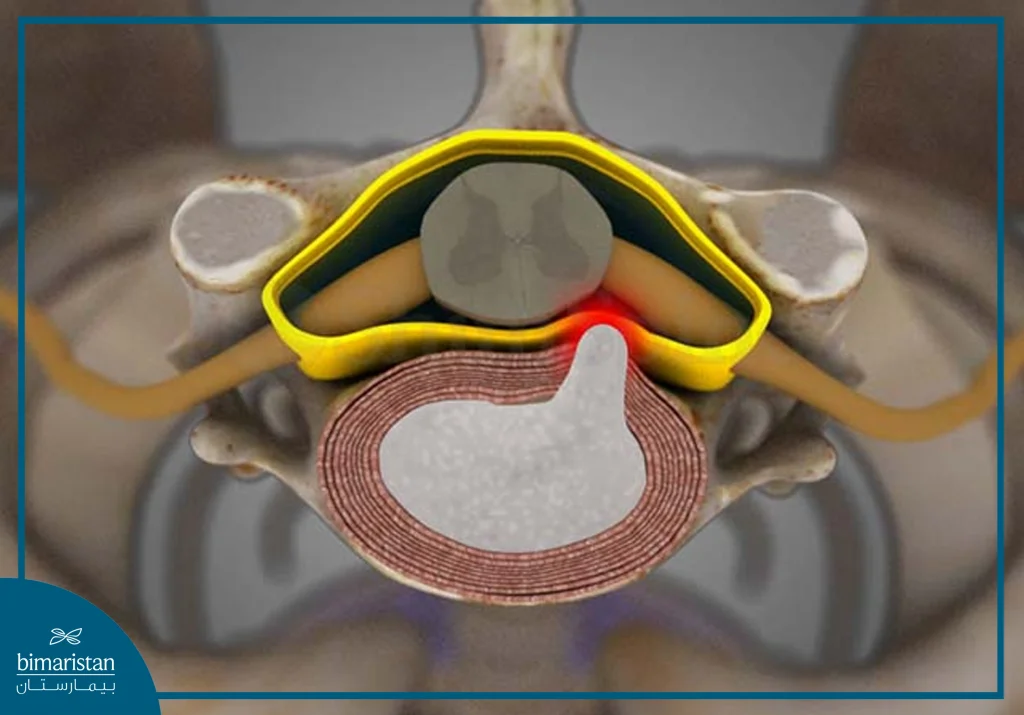

A neck disc or herniated disc is a common spinal disorder that results in protruding or ruptured intervertebral discs, causing direct pressure on the spinal cord, the nerve coming out from between the vertebrae, or both. This condition affects the patient’s daily life, as cervical discs have many symptoms that reduce the patient’s quality of life, most notably: